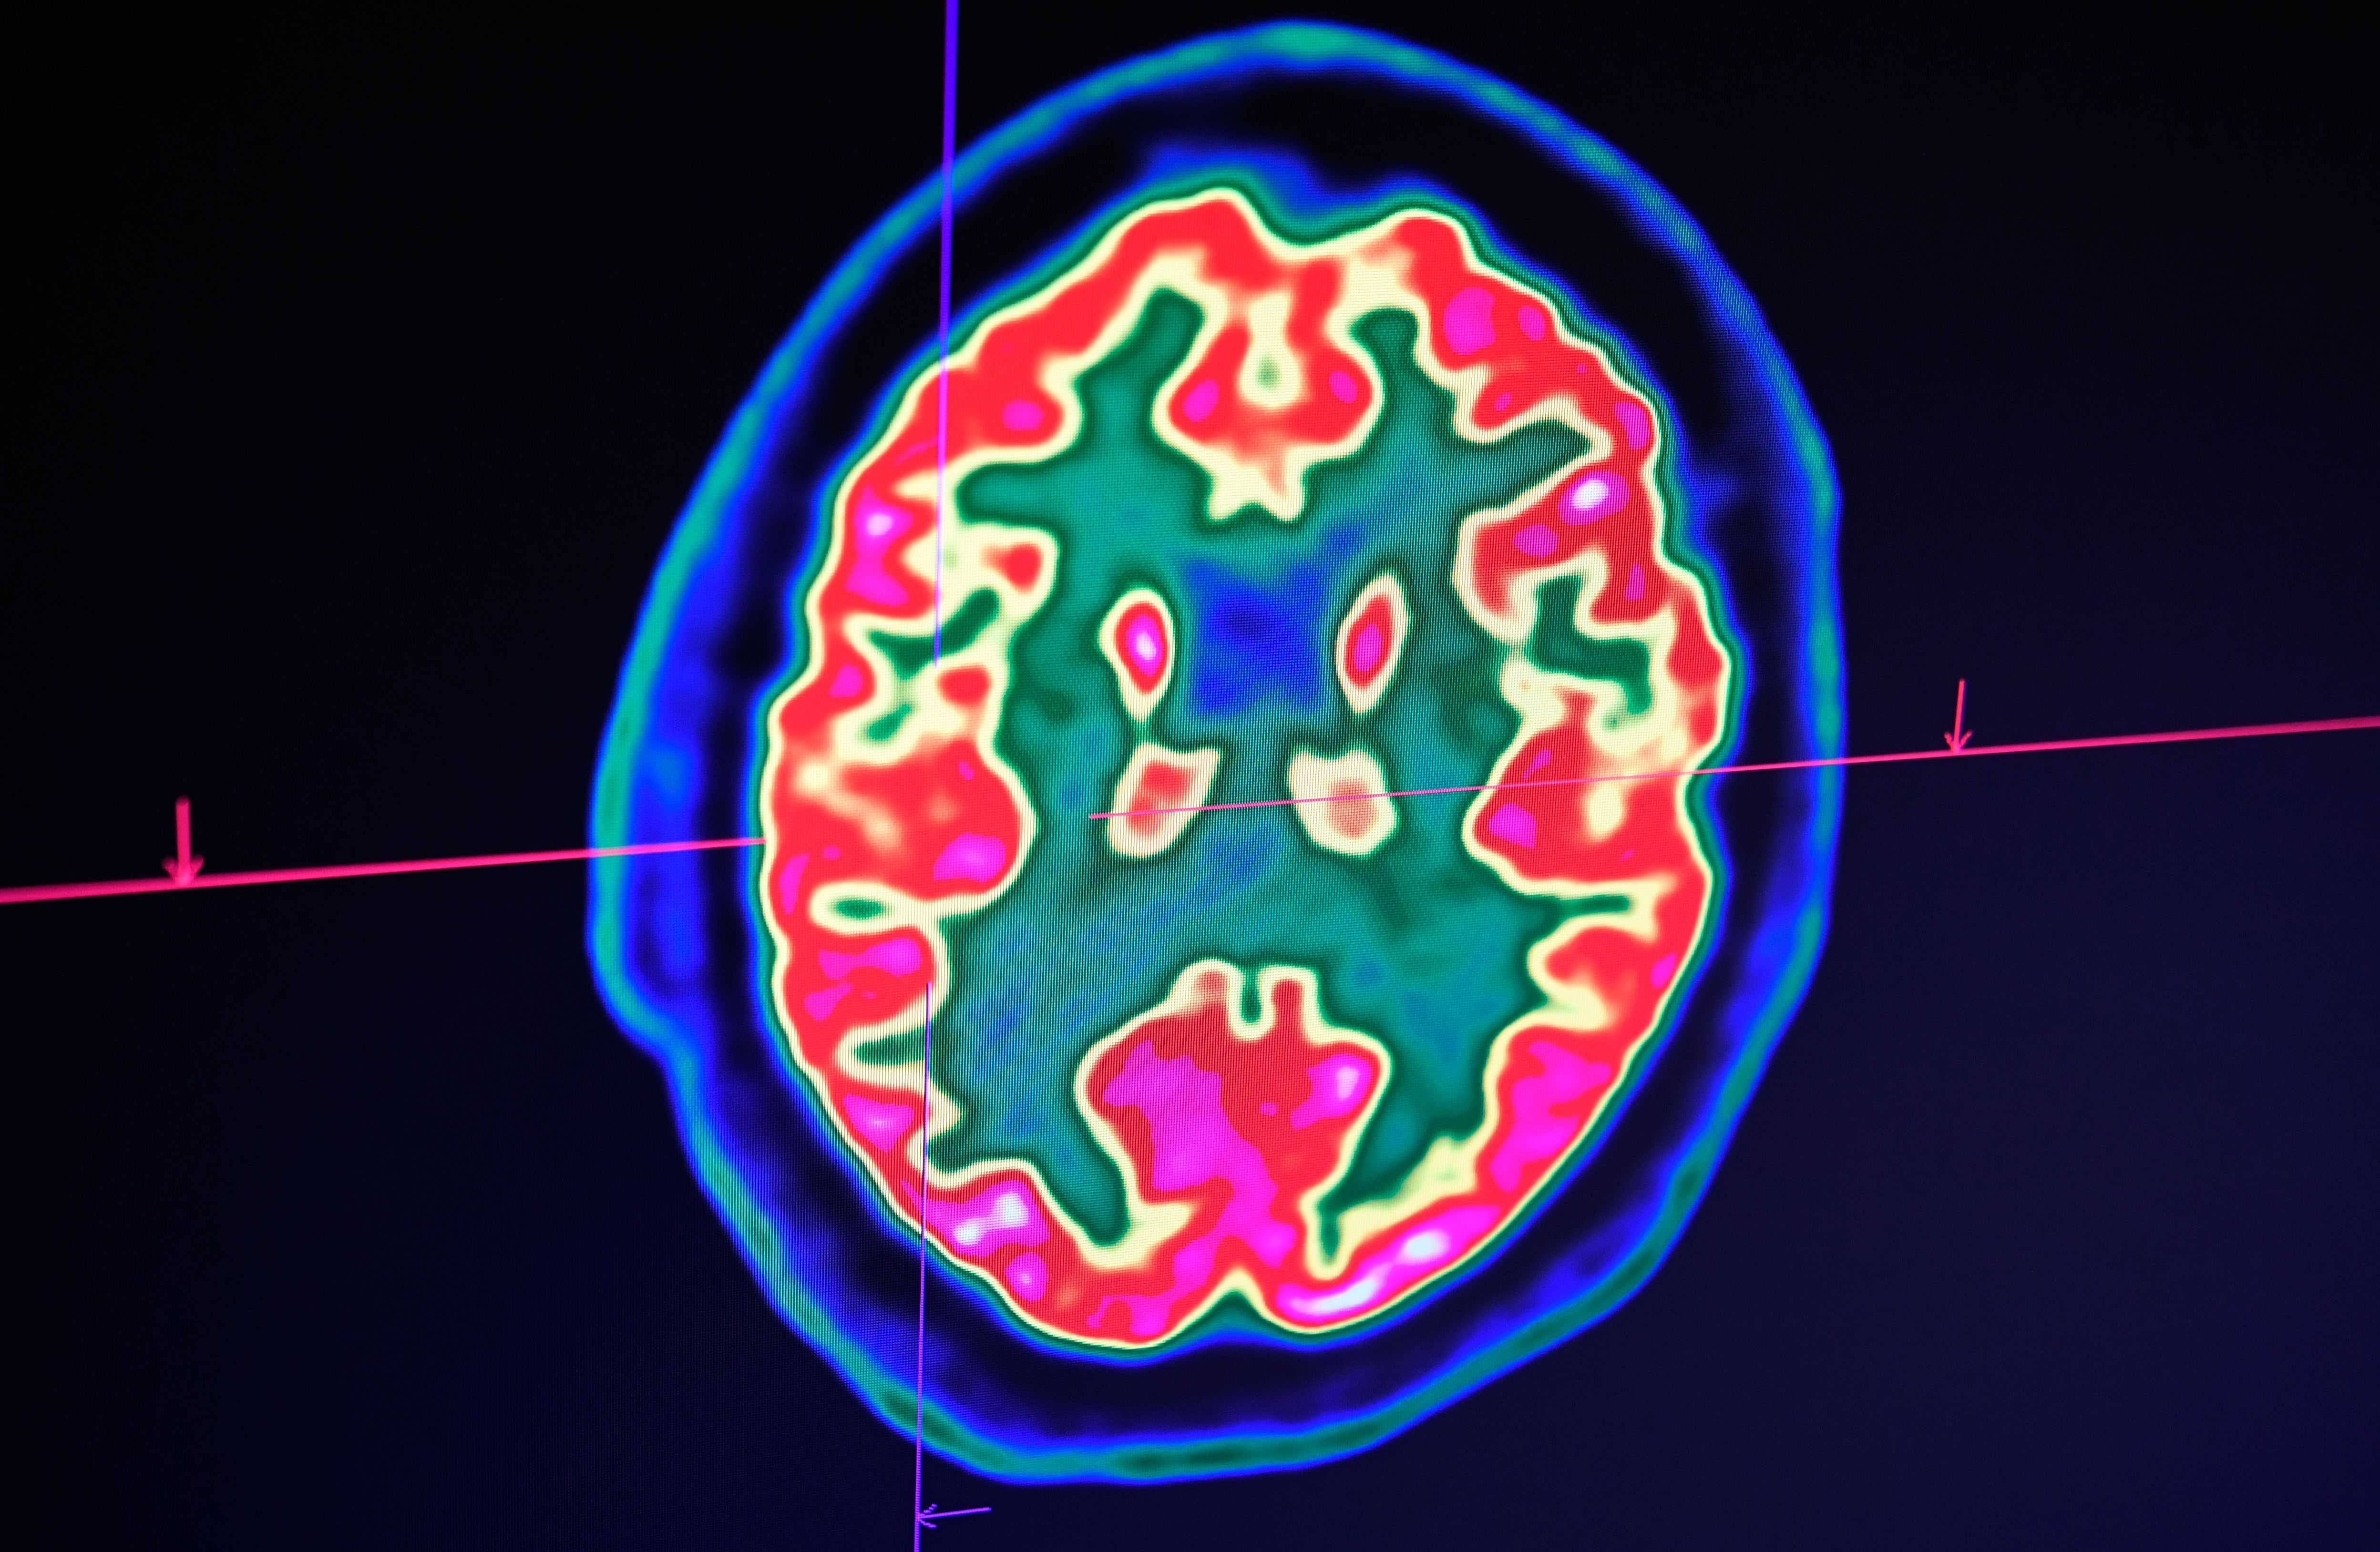

想不到諾亞2歲時已經能坐直身體、唱歌,打電腦遊戲!3歲時,腦部掃描顯示,他的大腦已經長回來,達到正常大小的80%。